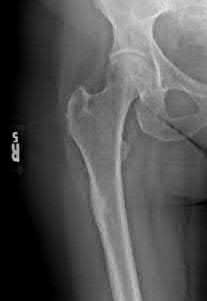

Question 20:

A 3-year-old girl is evaluated for severe, progressive bilateral genu varum. Radiographs demonstrate medial metaphyseal beaking, fragmentation, and depression of the proximal medial tibial physis. According to the Langenskiöld classification of infantile Blount's disease, at which stage does an overt physeal bony bar (epiphyseal-metaphyseal bridge) definitively form across the medial physis, conferring a high risk of recurrence without bar excision?

The Langenskiöld classification describes progressive radiographic changes in infantile Blount disease. Stage I-IV show worsening metaphyseal beaking and stepping. Stage V shows a deep cleft separating the medial epiphysis into two portions. Stage VI is definitively characterized by the formation of a solid medial physeal bridge (bony bar) between the epiphysis and metaphysis, halting medial growth completely and often requiring bar resection along with osteotomy.